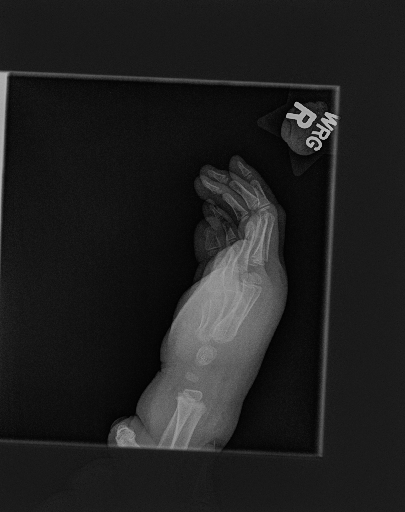

The first step in our pipeline is to detect the X-ray image carrier in the image. To this end, we apply OpenCV’s contour detection using Otsu binarization [14], and retrieve the minimum size bounding box, which does not need to be axis-aligned. This works sufficiently well as long as the majority of the image carrier is within the image (cf. Figure 3). However, the approach might fail for heavily tilted images or those where larger parts of the image carrier reach beyond the image border.

Hand Localization

To further improve the detection of hands, and in particular split the images where two hands are depicted on one image, we manually labeled approximately 150 bounding boxes in the images. Using this small dataset, we fine-tune a pre-trained single shot multibox detector (SSD) [12] with MobileNet as taken from TensorFlow. An exemplary results can be seen in Figure 3.